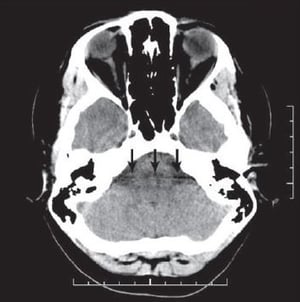

Artifact streaking is visually self-explanatory, but the causes bear some explanation. Most streak artifacts occur near materials such as metal or bone, primarily as a result of beam hardening and scatter.

These phenomena produce dark streaks between metal, bone, iodinated contrast, barium, and other high-attenuation materials. Bright streaks are seen adjacent to the dark streaks2. See an example of an artifact caused by beam hardening below.3